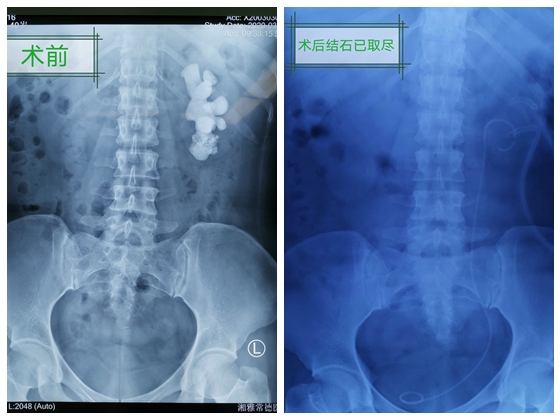

40岁的郭女士,20多年前查出患有肾结石。因害怕做手术,一直没有复查与处理。今年3月初,郭女士突然发现自己的尿液变红,出现血尿,特地前往长沙做了检查,一看结果吓一跳:原来左肾结石已经长大了很多,基本占满整个肾脏,像一块生姜!

郭女士非常担心与害怕,辗转多家医院,最后来到湘雅常德医院泌尿外科。顿金庚主任接诊了郭女士,阅CT片后详细介绍说:这样大的结石是不常见的,结石基本填满了肾脏空间,称作鹿角形结石,而且结石分布在肾脏各个角落,虽然想把结石取干净比较困难,也很可能需要多次手术并且手术有一定的风险,虽我们医院虽开业仅仅两年多,但已经成功处理了多例这样的大结石。

郭女士和丈夫商量后,打消疑虑下定决心:要取出长在肾脏里二十多年的结石。通过完善检查、抗感染、补充营养等术前准备,在顿金庚主任的指导下,术前详细讨论制定手术方案后,由结石组组长陈旭东副主任医师主刀及朱敏主治医生的配合,术中通过精准B超定位穿刺、造瘘,仅仅通过两根筷子一般大的小孔,钬激光、气压弹道碎石双管齐下,不到一百毫升的极少量出血,取出了一小盆结石,顺利完成手术。